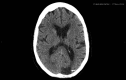

A 71-year-old lady presented with a symptomatic left cerebral occipital lobe infarct. With a history of paroxysmal atrial fibrillation a cardioembolic source was initially postulated. Prior significant bleeding while anticoagulated precluded warfarin therapy. Further investigations revealed a critical left internal carotid stenosis with a persistent fetal origin of the left posterior cerebral artery. She was successfully treated surgically and suffered no further ischaemic events. Physicians encountering posterior circulation stroke should be aware of this potentially treatable important diagnosis.